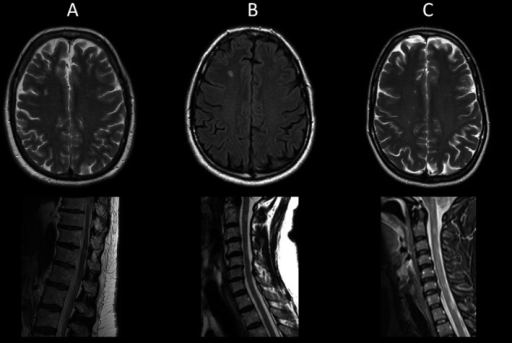

Brain And Spinal Cord Mri Abnormalities In Three Patien Open I from openi.nlm.nih.gov

Imaging of the spine in multiple sclerosis.